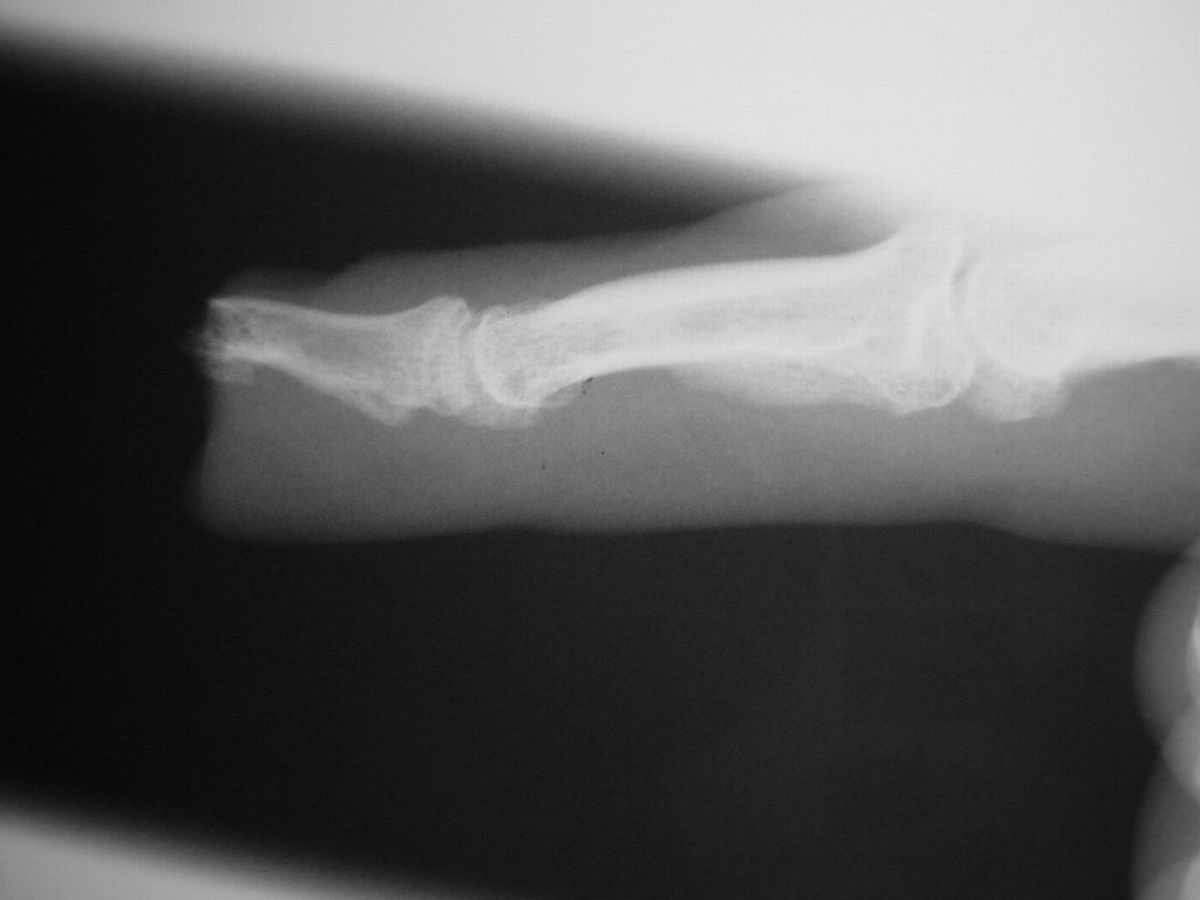

| Case

4. A dog bit off this young man's index fingertip. Although the PA Xray looks as though the bone was kept, additional views show an amputation through the tuft. |